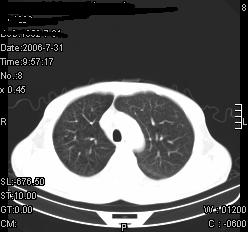

患者,男,54岁,咳嗦,咳痰20天。抗炎治疗2周。现esr76mm/h,目前患者症状明显好转,但发现两次ct片未见明显变化。两次分别做与7.25、7.31。第一次诊断右肺上叶炎症累计胸膜。大家看,从影像上内排除结核吗?

结核的可能性非常大,右上肺病变应该考虑干酪性肺炎。理由:

1.纵隔内多发淋巴结肿大。

2.esr76mm/h。

3.虽经抗炎治疗肺窗病灶有所吸收、减小,但纵隔窗病灶形态、密度、范围无明显变化。如果是单纯的大叶性肺炎,“抗炎治疗2周,目前患者症状明显好转”病灶应该基本消散了,至少也处于吸收消散期,密度变淡、范围变小。同时本病例所示其内的密度不均匀,见多发大小不一空洞样影也不符合大叶性肺炎吸收消散期表现。

病灶特点:片状 索条 结节混杂影,部分融合,密度不均,广泛累及相应胸膜.

临床治疗;二周未吸收.但症状好转.

多考虑:肺结核.